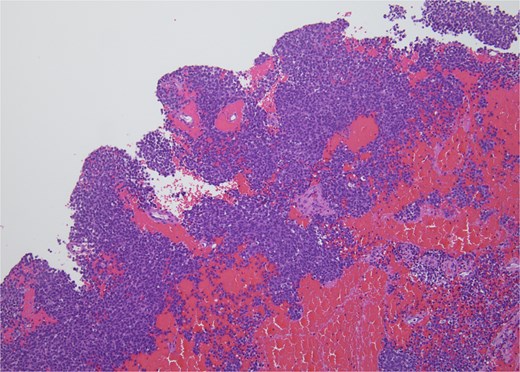

Histopathology revealed small, round, blue cells (Fig. 2), and other findings consistent with ES (Fig. 3).

H&E, 40×. The neoplastic cells have scant cytoplasm, finely stippled chromatin, and inconspicuous nucleoli. At high power, mitotic figures and apoptotic debris are visible.